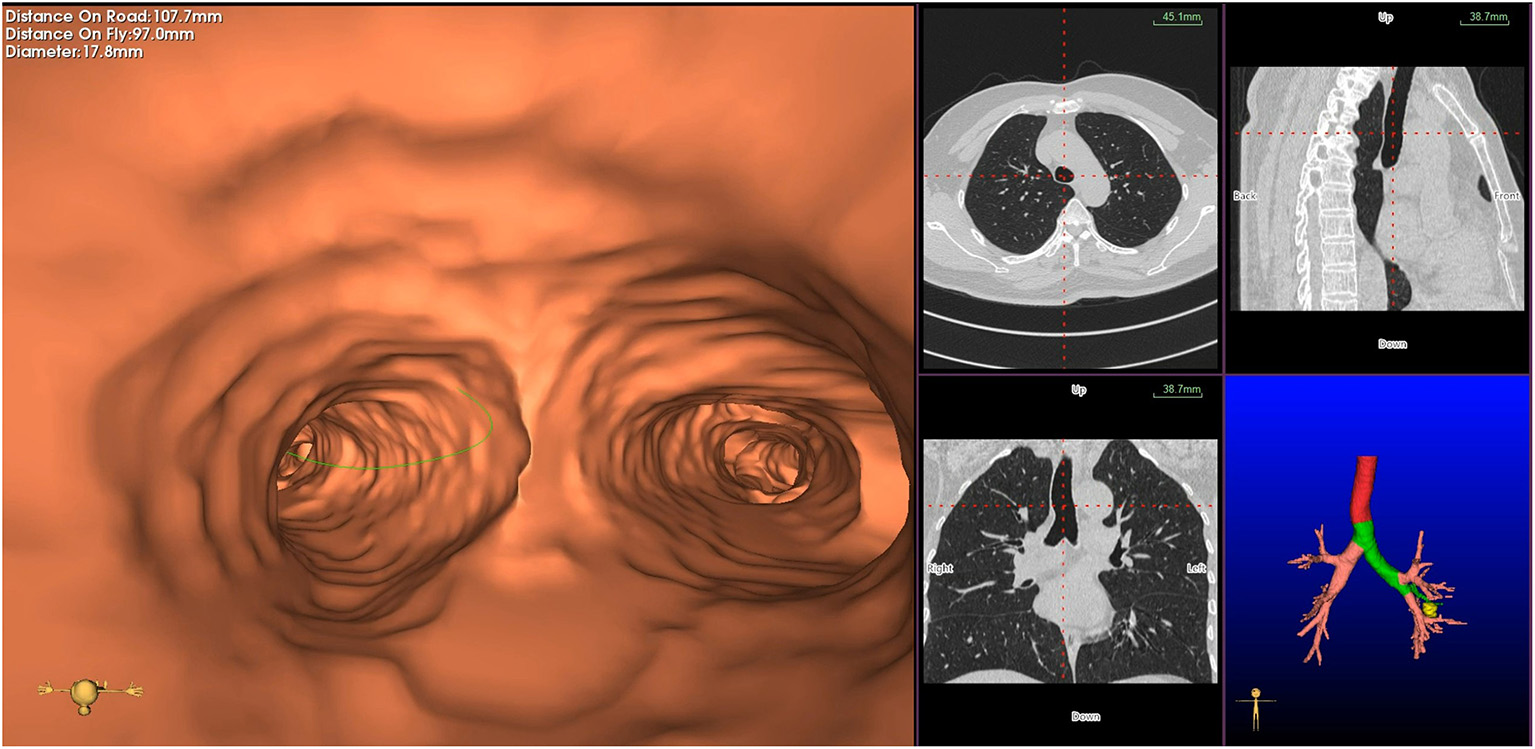

Virtual bronchoscopic navigation is a navigational technique that utilizes data of helical CT to construct three-dimensional virtual images of the bronchial route to guide the bronchoscope to the target lesion (Figure 1). Bf-NAVI® (Cybernet System Inc., Tokyo, Japan) was the first VBN system that was introduced in Japan in 2008, LungPoint® (Broncus Medical Inc., Mountain View, CA, USA) was launched in 2009 in the USA and is now widely used in the USA and European countries (10). DirectPath® (Cybernet System Inc.), which has replaced Bf-NAVI, is used in China by most centers. There are mainly 3 phases of virtual bronchoscopic navigation: planning, guidance, and biopsy. (i) Planning phase: In the planning phase, data from multi-detector chest CT of patients are imported to the computer via VBN software (Figure 2), which automatically creates the virtual bronchoscopic pathway to the target lesion (Figure 3). To obtain high-quality virtual bronchoscopic (VB) images, continuous volume CT data is required. Planning is a pre-bronchoscopy process that is usually done on the same day or days before the intended biopsy. (ii) Guidance phase: The virtual images acquired during the planning phase are used to advance the bronchoscope manually to the target lesion, and the position of the bronchoscope tip can be displayed on the CT images corresponding to the bronchial tree. (iii) Biopsy phase: The choice of procedure to biopsy lesion depends on patient selection and target disease. PPLs can be sampled with flexible bronchoscopy, ultrathin bronchoscopy, and radial endobronchial ultrasound probes (RP-EBUS).

Figure 1

Virtual bronchial path (fly through) to the target peripheral pulmonary lesion (green line represents bronchial path).